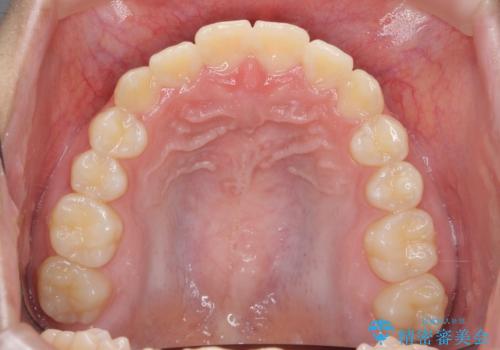

インビザラインで行う八重歯の治療

- 笑った時に目立つ八重歯の矯正治療を求めて来院されました。

マイクロインプラントを用いた臼歯の後方牽引、およびゴムかけ等の付加処置を駆使して八重歯の治療を行っていきます。

しっかりとゴムかけを頑張っていただいたおかげで、上顎臼歯の後方移動が達成されしっかりとした噛み合わせの構築と、八重歯の治療を達成することができました。